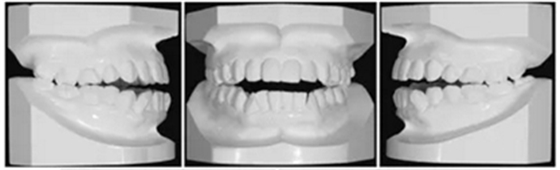

面部照片顯示,患者為凸面型,鼻唇時頦肌緊張(Figure 3)??趦?nèi)檢查顯示雙側(cè)第二前磨牙間開合(Figures3 and 4)。覆合覆蓋分別為-3.5mm和+1.2mm。正面觀,上下牙列中線與面部中線一致。雙側(cè)磨牙II類關(guān)系,下前牙區(qū)中度擁擠。